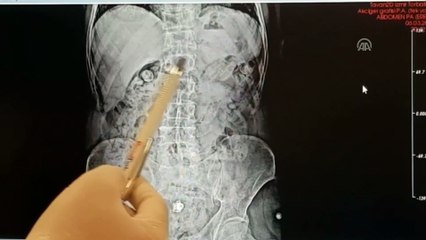

İran uyruklu şüphelilerin midelerinden uyuşturucu çıktıERZİNCAN Erzincan polisinin yaptığı yol uygulaması sırasında durdurulan otobüste, uyuşturucuyu midesine gizleyen İran uyruklu 3 kişi tutuklandı. brİran uyruklu şüphelilerin midelerinden uyuşturucu çıktıbrERZİNCAN Erzincan polisinin yaptığı yol uygulaması sırasında durdurulan otobüste, uyuşturucuyu midesine gizleyen İran uyruklu 3 kişi tutuklandı. br Alınan bilgiye göre, İl Jandarma Komutanlığı ekiplerince geçtiğimiz 29 Mart 2023 tarihinde Üzümlü ilçesi D-100 karayolu üzerinde durdurulan İran plakalı bir yolcu otobüsünde yolculuk yapan İran uyruklu M.S. (27), M.H (42), ve S.A isimli 3 şüpheli kişinin iç beden muayeneleri sonucunda, yutmak suretiyle uyuşturucu kuryeliği yaptıkları belirlendi. Haberabr br hbrlr1.